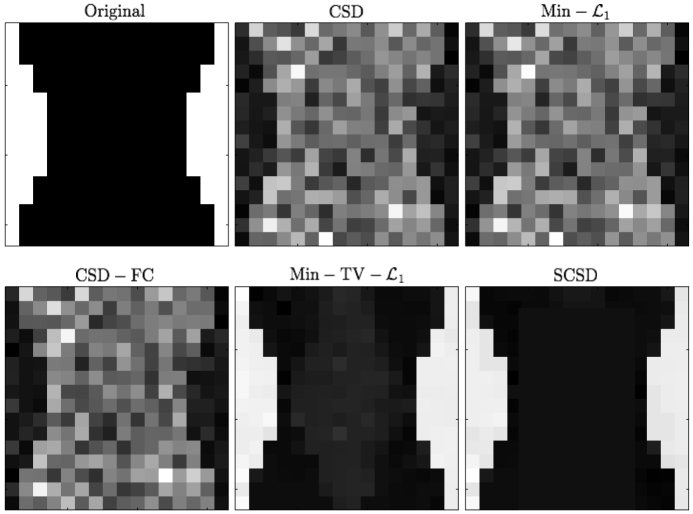

The results of our final quantitative comparison are summarized in Fig. 7, which shows the values of contrast obtained using different SD methods under comparison for s/mm2 (left column of subplots) and s/mm2 (right column of subplots). Predictably enough, the best contrast is achieved by the Min-TV- and SCSD algorithms, owing to their inherent ability to account for the presence of isotropic diffusion. Moreover, out of the two, the proposed SCSD algorithm yields the higher values of for all simulated scenarios. An additional illustration of the effect of incorporation and spatial regularization of the isotropic diffusion component is provided in Fig. 8, which depicts a 2-D “axial” slice of the IDMs reconstructed by different SD methods under comparison for s/mm2, , and . (Note that, for the sake of the clarity of visualization, the IDMs in Fig. 8 have been normalized so as to make their minimum and maximum values correspond to black and white pixel values, respectively.) One can see that the IDM reconstruction produced by SCSD is virtually indistinguishable from the original IDM (as shown in the upper, leftmost subplot of the figure), with the second best result produced by the Min-TV- algorithm. At the same time, neither CSD, Min- nor CSD-FC can attain a comparable accuracy of estimation of the spatial pattern of isotropic diffusion, as represented by the original IDM. In particular, even though their respective reconstructions do bear some global resemblance to the original IDM, the level of estimation errors is too high to deem these reconstructions useful.